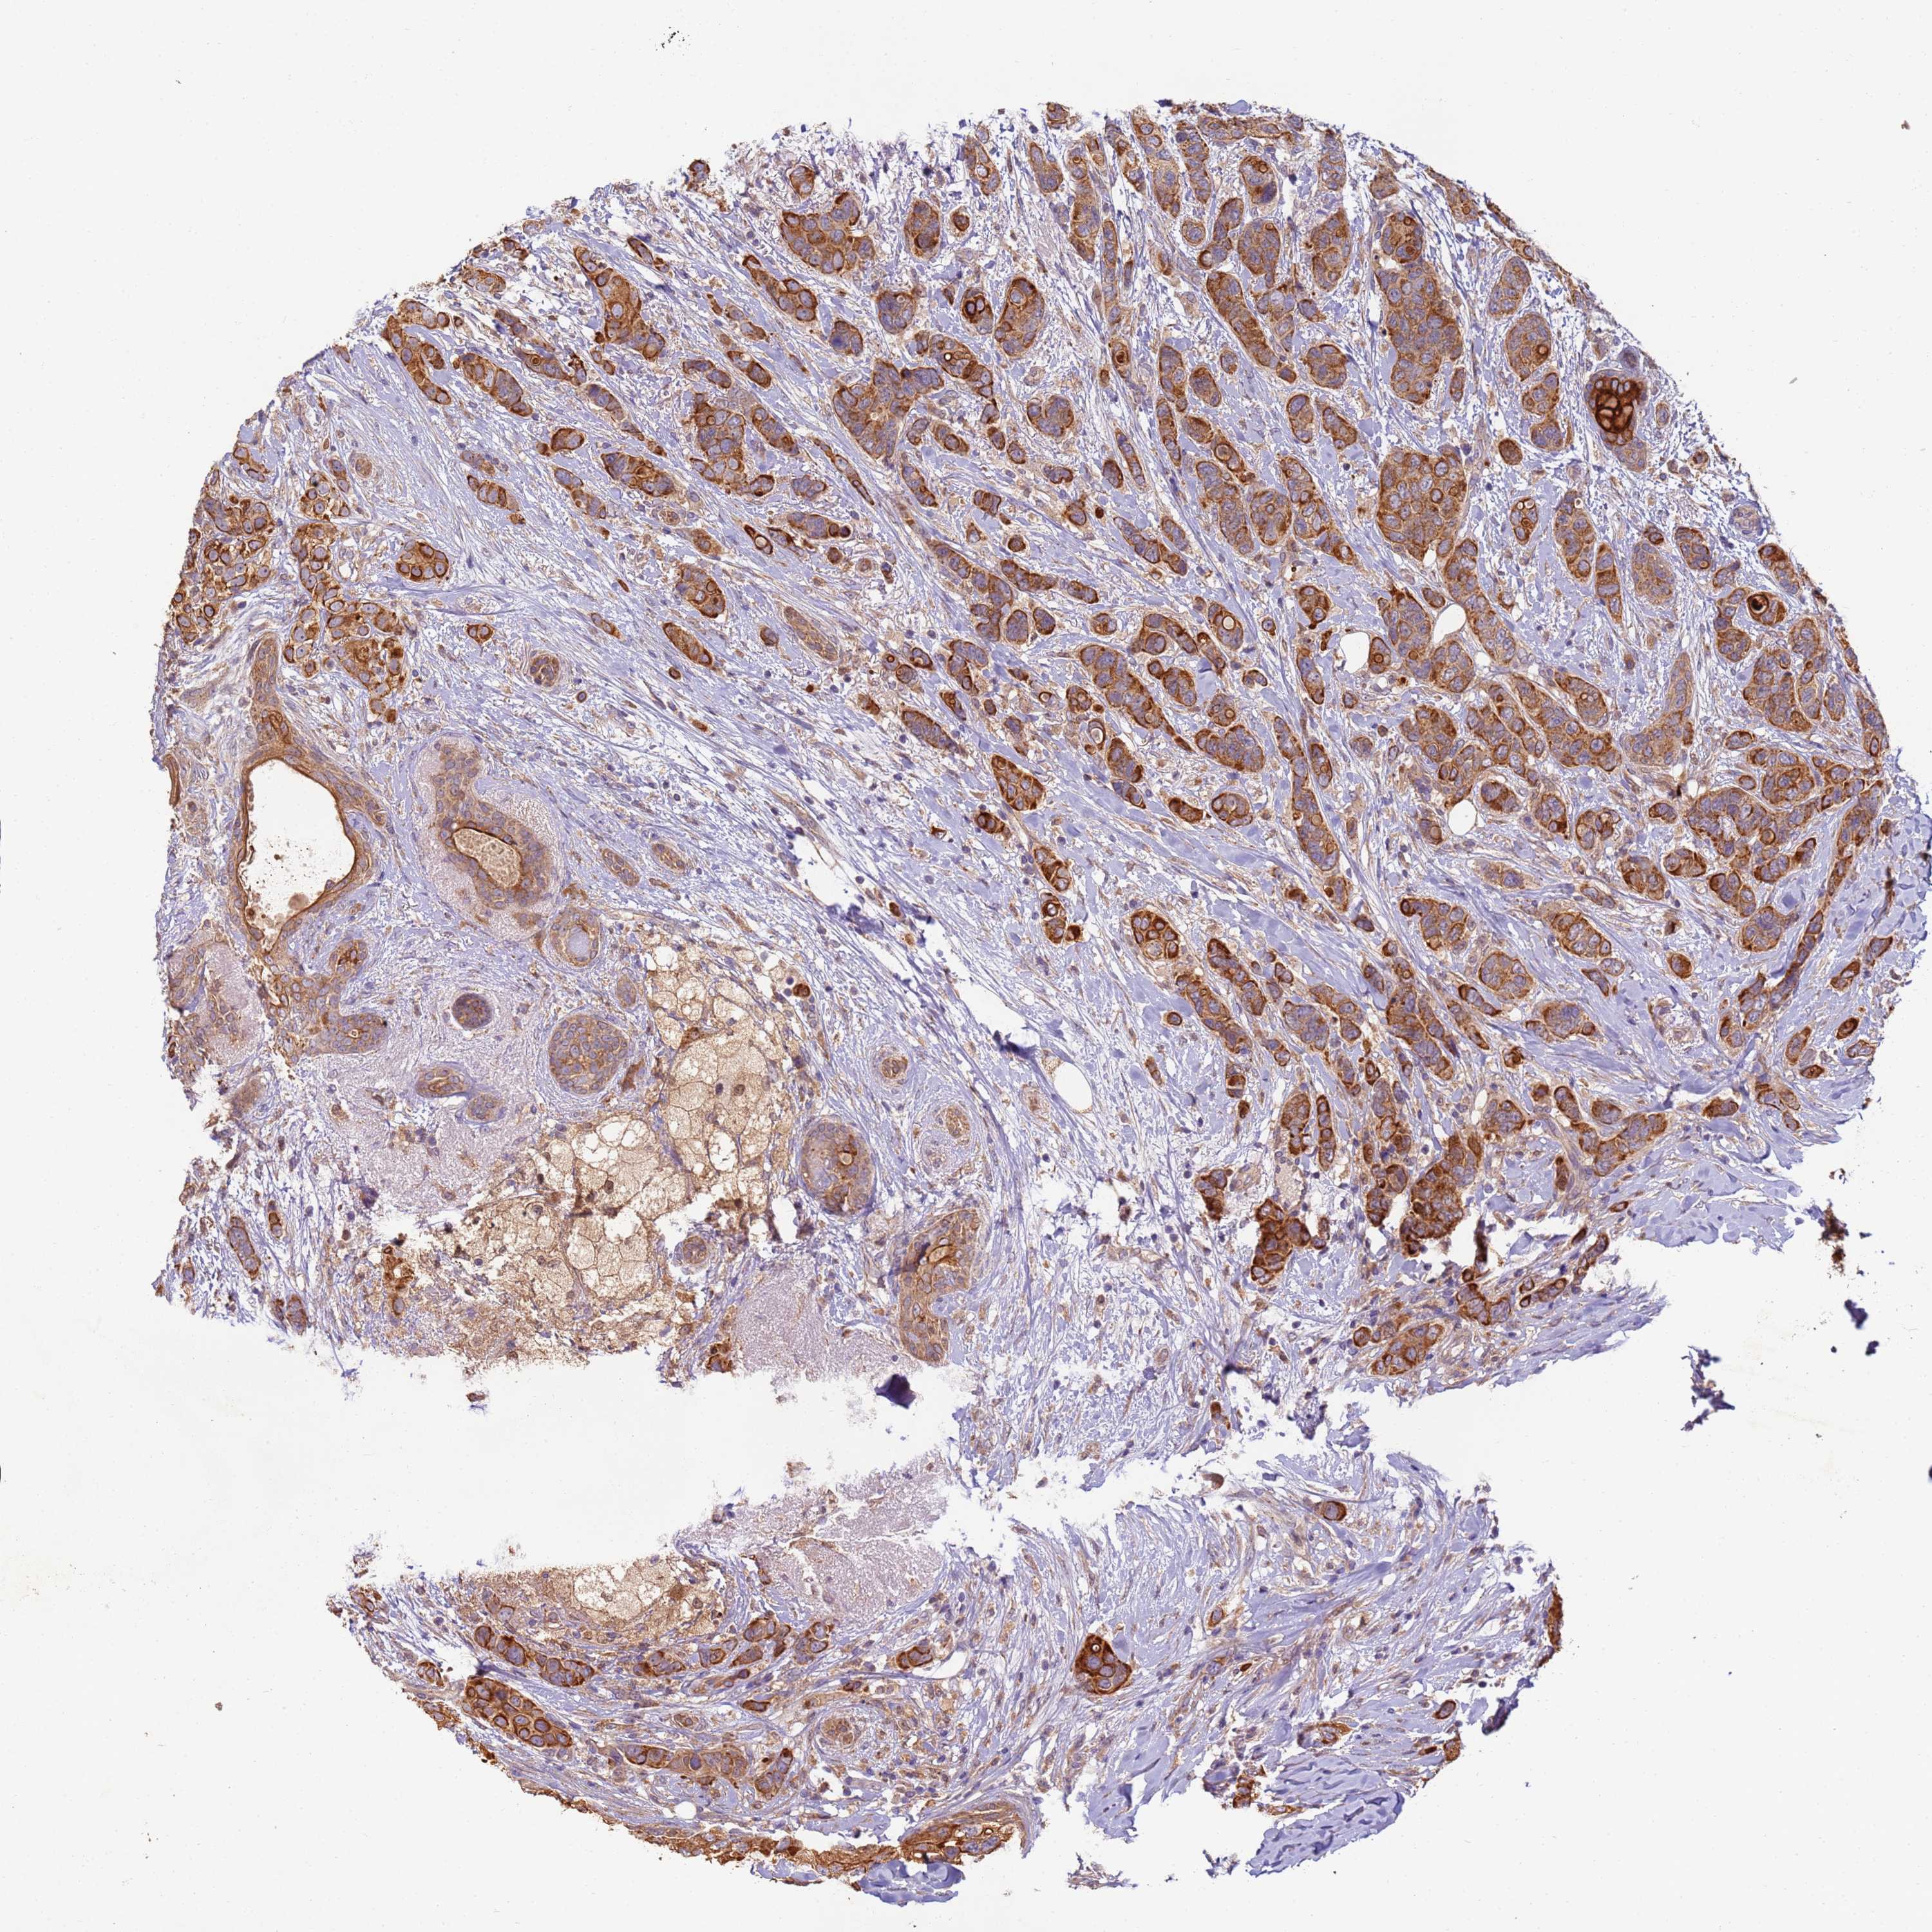

CANCER BREAST CANCER Show tissue menu

BRCA TCGA BRCA VALIDATION PROTEIN EXPRESSION